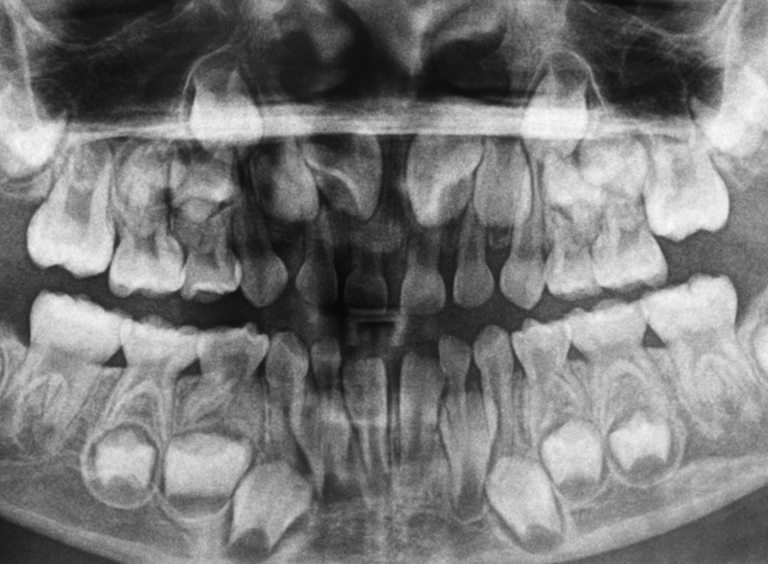

Детето разполага с 20 млечни зъба - 10 отгоре и 10 отдолу, под които са разположени зачатъците на бъдещите постоянни зъби. Първи се показват долните предни резци, а последни - кътниците. Редът на падането им е същият.

Но едно от най-важните им предназначения е да пазят място за постоянните зъби, които ще ги заместят по-късно.

Когато по някаква причина се наложи преждевременното отстраняване на някое млечно зъбче, постоянният зъб губи мястото си и това води до струпване и разкривяване на новите зъби. Възможно е и поникването на постоянния зъб да се забави, ако след отстраняването на млечния се е натрупала костна тъкан, която пречи на това.

Може би сте се питали защо просто от самото начало не ни поникват постоянни зъби, а трябва да ги сменяме. Това е така, защото размерът на челюстта на детето е твърде малък за големите постоянни зъби. А ако оставаха с размера на млечните, при възрастния индивид те щяха да бъдат малко на брой и с големи разстояния помежду си.